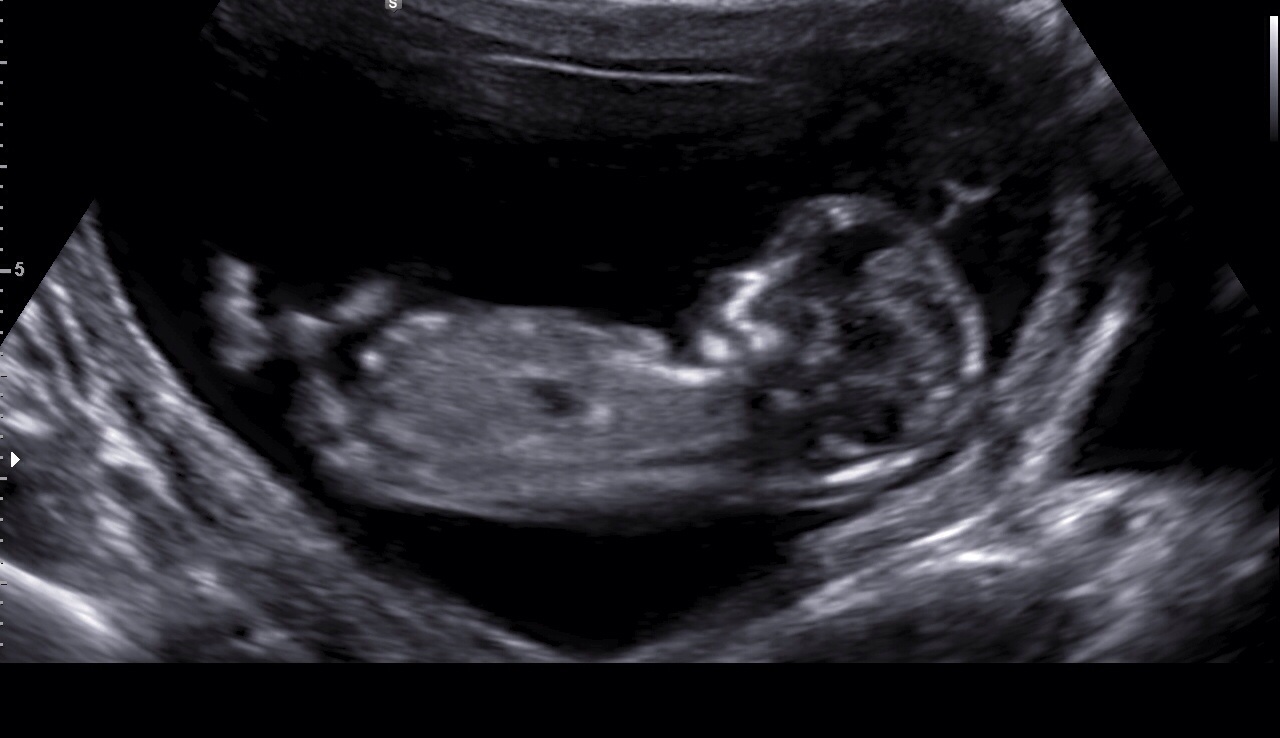

12w3d ultrasound :)

So fun to see baby moving around, kicking arms and legs, and opening and closing his/her mouth!

Baby was also bouncing all over!!